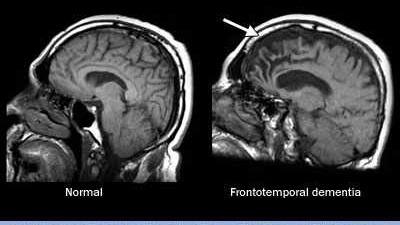

As the name suggests, FTD affects the frontal lobe and/or temporal lobes of the brain. Signs and symptoms vary, depending on which part of the brain is atrophying, or shrinking. Genetic mutations and dysfunctional proteins in the brain have been linked to FTD.

Brain imaging tests are important. An MRI scan may show shrinking of the frontal or temporal lobes of the brain. A PET scan may show metabolic changes in these same regions of the brain.